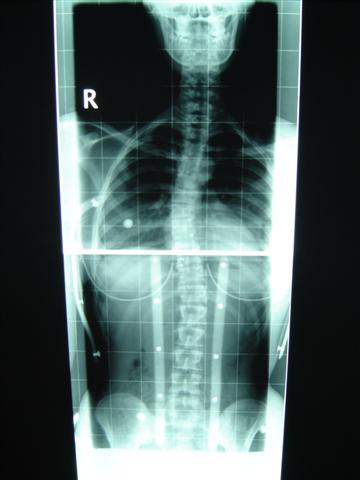

Ja im Tageskorsett wurde ich im Stehen geröngt. Das erste Röntgen war bei mir in Guben gewesen und als ich dann zum ersten Mal in Dresden war, wurde ich nochmal geröngt, weil der Arzt gleich meinte, dass es sich verschlechtert hat. Und dann bekam ich erst die Korsetts. Das Nachtkorsett korrigiert nicht nur meine untere Krümmung, sondern auch die obere. Bei mir ist das problem, dass meine Skoli sehr weit oben anfängt und deshalb der linke Arm noch mehr angeoben werden müsste als üblich, nur bei mir ist er schon nach 2 min im Korsett bei der Anprobe eingeschlafen. Da wurde dann ein neues Korsett gebaut für den Tag, das sich halt fast nur auf die untere Krümmuing konzentriert. Ich sollte ja ursprünglich nur das eine Korsett haben, aber damit die obere Krümmung auch korrigiert wird, bekam ich noch ein Nachtkorsett. Und im Liegen geht das bei mir, da nehm ich den Arm sozusagen noch ein Stückchen hoch und wenn ich auf der Seite liege gehts sowieso, da schläft der Arm nicht ein.

Meine obere Krümmung beträgt ohne Korsett 34° und im Korsett hat der Arzt 18° ausgerechnet. Aber die Krümmung wird ja eig. gar nicht wirklich korrigiert, und der Bogen fällt einem doch ins Auge, wenn man die anderen 12° sieht.

ImTageskorsett 1.JPG (21.96 KiB) 9663 mal betrachtet